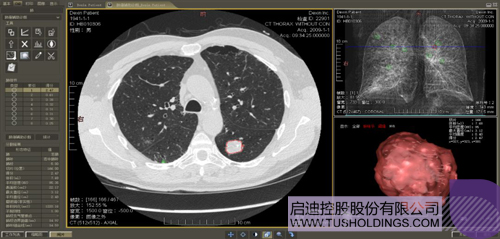

醫(yī)療影像智能分析是指運用人工智能技術、計算機視覺技術以及計算幾何技術對醫(yī)療影像進行自動分析,幫助醫(yī)生定位病癥、分析、跟蹤病情,并通過量化數(shù)據(jù)輔助醫(yī)生做出診斷,目前其旗艦產(chǎn)品“數(shù)字肺”已經(jīng)覆蓋多種肺部疾病的早期檢測、診斷、跟蹤、術前規(guī)劃等完整的醫(yī)療流程。在臨床實踐中,超過80%的醫(yī)療數(shù)據(jù)來自醫(yī)療影像,這些影像數(shù)據(jù)通常需要專業(yè)醫(yī)生進行解讀,工作的重復性高、效率偏低。如果能夠運用智能影像分析技術,同時結合臨床表現(xiàn)以及既往病例進行全面分析,那么就可以大幅度提升影像診斷效率和準確性,讓專業(yè)醫(yī)生的寶貴時間集中在復雜病情的診斷和治療等環(huán)節(jié)。

數(shù)字肺——肺結節(jié)手術規(guī)劃系統(tǒng)

肺動脈栓塞輔助診斷